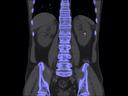

More and more radiologists are relying on the rich diagnostic possibilities offered by True Dual Energy imaging on Siemens Healthineers' CT scanner fleet ranging from SOMATOM® Scope Power up to the outstanding SOMATOM Force.

The question is: What makes True Dual Energy stand out? Look for these three criteria: crisp images with the option for even sharper contrast and significant artifact reduction; no extra dose in either Single Source or Dual Source Dual Energy scans, and a broad applicability for virtually all clinical questions and patients.

Discover Dual Energy (DE) spectral imaging. It’s the difference between images and answers. Visualization and characterization. Qualification and quantification. Built into all of our CT scanners, it delivers powerful performance, incredible versatility for your entire patient population, and exceptional ease-of-use – all while integrating seamlessly with your current workflow.